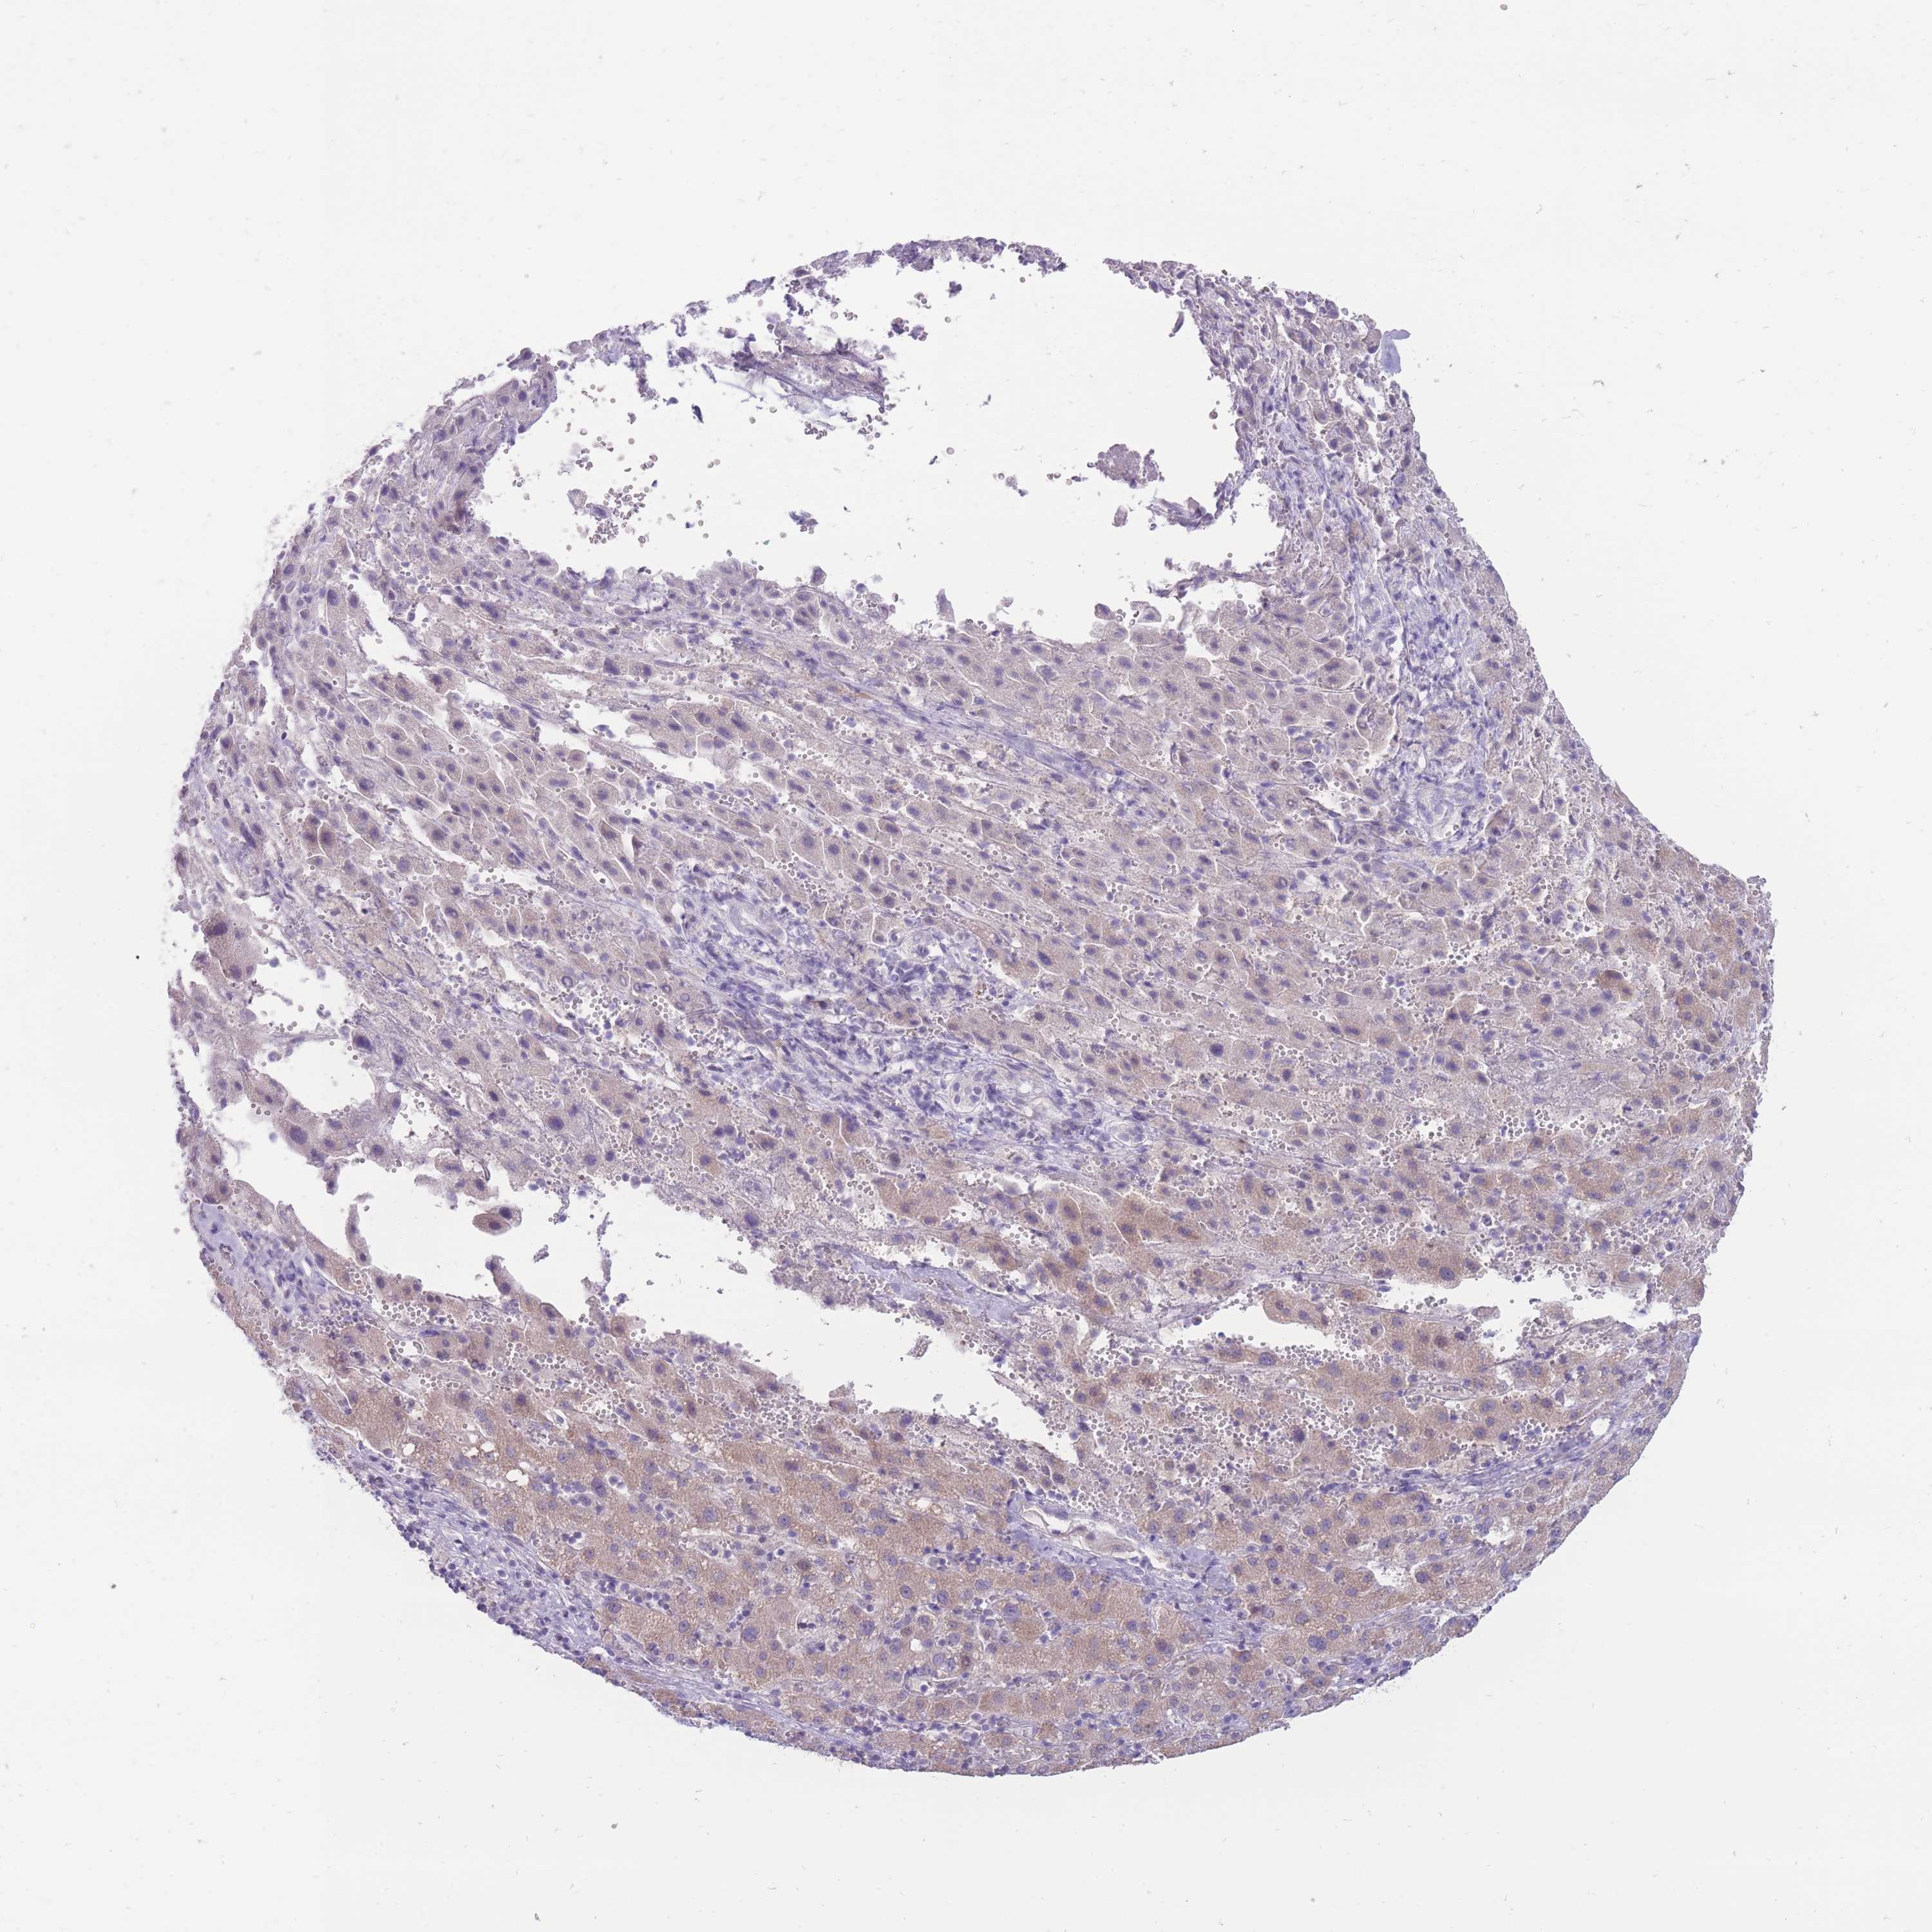

LIVER CANCER - Protein expressioni

A mouse-over function shows sample information and annotation data. Click on an image to view it in a full screen mode. Samples can be filtered based on level of antibody staining by selecting one or several of the following categories: high, medium, low and not detected. The assay and annotation is described here.

Note that samples used for immunohistochemistry by the Human Protein Atlas do not correspond to samples in the TCGA dataset.

Antibody stainingi

Antibody staining in the annotated cell types in the current human tissue is reported as not detected, low, medium, or high, based on conventional immunohistochemistry profiling in selected tissues. This score is based on the combination of the staining intensity and fraction of stained cells.

Each image is clickable and will lead to virtual microscopy that enables deeper exploration of all samples and also displays staining intensity scores, fraction scores and subcellular localization as well as patient and tissue information for each sample.

Antibody HPA042632

Antibody HPA048484

Staining

High

Medium

Low

Not detected

Intensity

Strong

Moderate

Weak

Negative

Quantity

>75%

75%-25%

<25%

None

Location

Nuclear

Cytoplasmic/membranous

Cytoplasmic/membranous,nuclear

Cholangiocarcinoma

Carcinoma, Hepatocellular, NOS